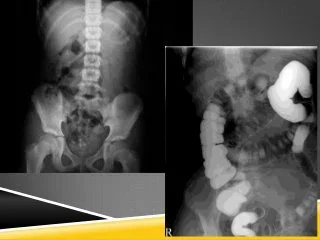

• USO DE CONTRASTES

USO DE CONTRASTES

El Italiano Dutto, realizó investigaciones de anatomía en cadáveres inyectandolas arterias e identificándolas radiográficamente con una sustancia llamada yeso de París.